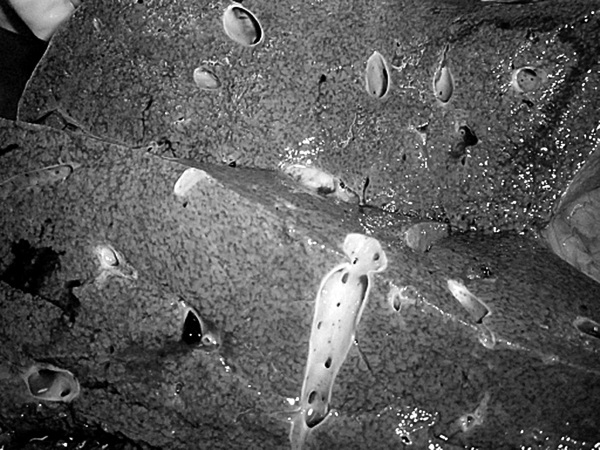

На секции был установлен следующий диагноз.

Основной:

1. Последствия инфаркта головного мозга. Внутренняя гидроцефалия. Атеросклероз артерий виллизиева круга.

2. ИБС. Постинфарктный кардиосклероз. Атеросклероз коронарных артерий.

Фоновый:

1. Артериальная гипертензия.

2. Гипертрофия левого желудочка сердца.

Осложнения:

1. Длительная иммобилизация.

2. Хроническая сердечная недостаточность.

3. Невроангиосклероз.

4. Пролежни.

5. Интоксикация.

6. Отек головного мозга.

Сопутствующий:

Доброкачественная гиперплазия предстательной железы

Последствия ОНМК: постинфарктные кисты головного мозга

Постинфарктный кардиосклероз

Атеросклероз сосудов головного мозга. Отек головного мозга

Атеросклероз коронарных артерий

Гипертрофия левого желудочка

Мускатная печень

Полнокровные легкие

Рис. 1. Результаты аутопсии больного 68 лет